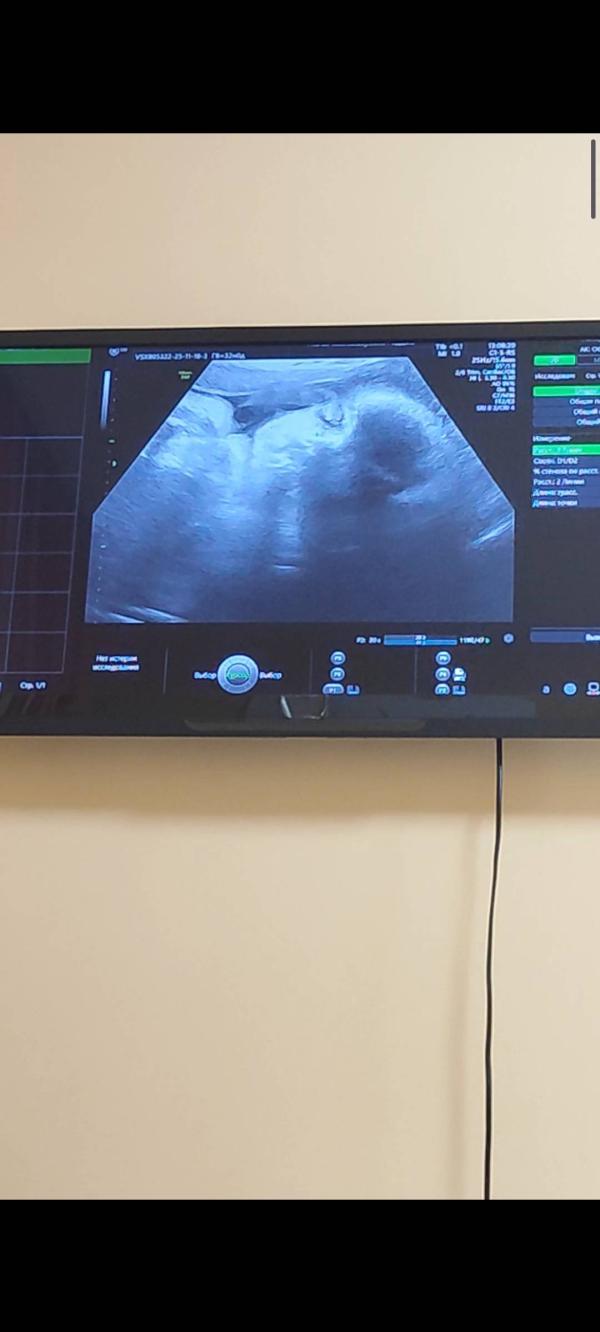

Пройден последний скрининг ✅

32 неделя, 🥰 2кг счастья, пдр 13 января. Все сформировано ☺ Бьет по почкам ножками 👣😆